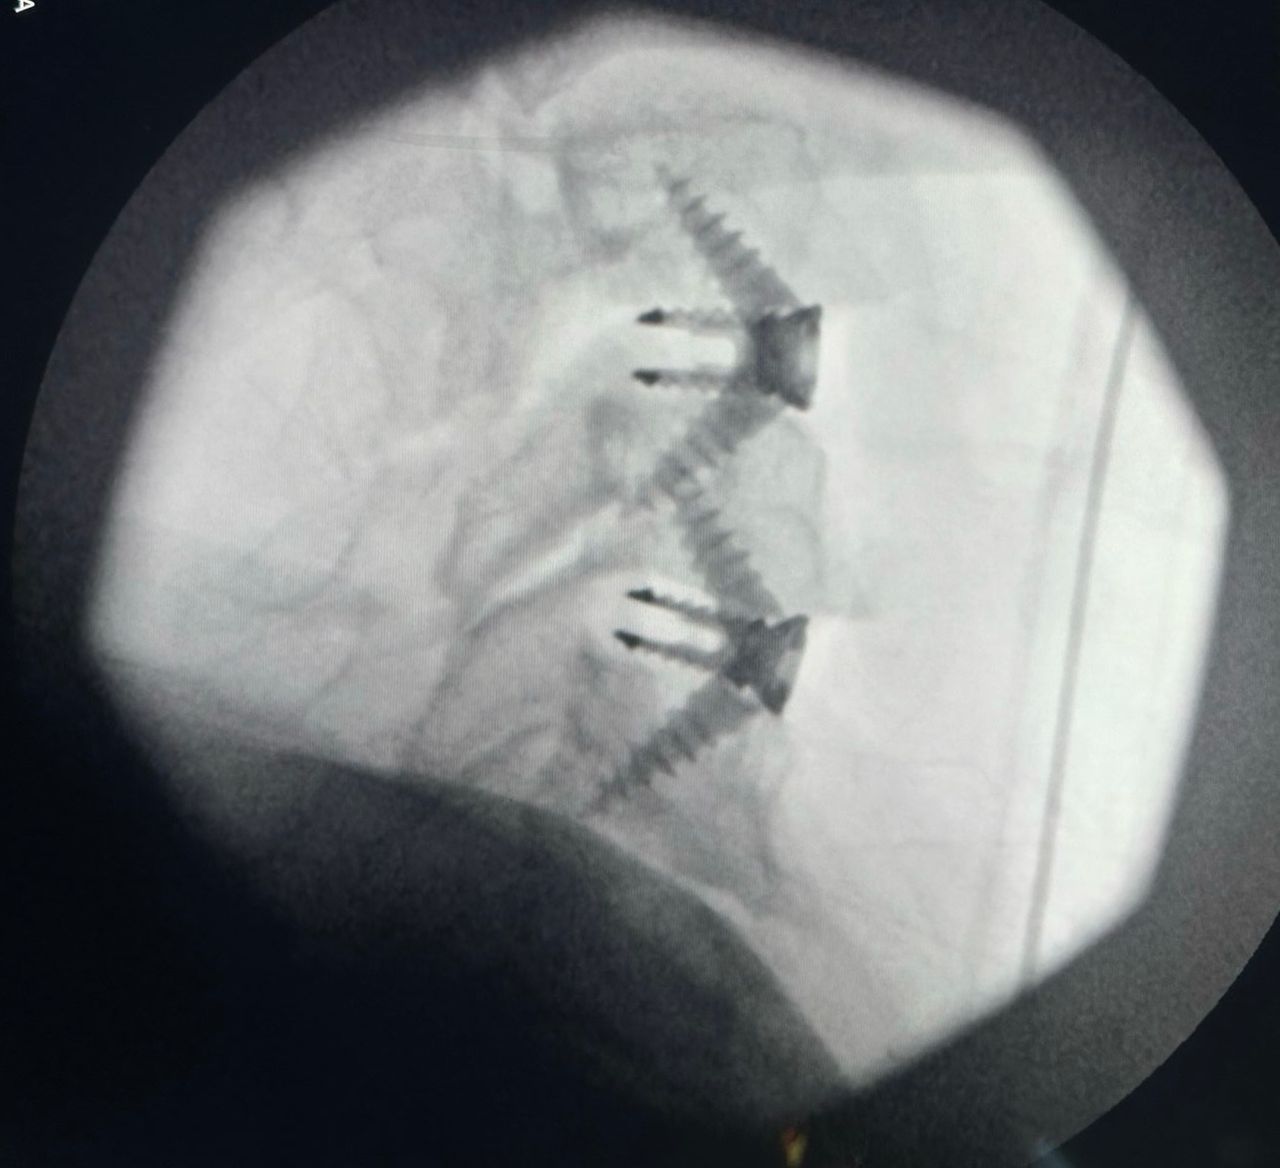

Cirugía de columna por mínima invasión

Estabilización y fusión lumbar con tornillos transpediculares